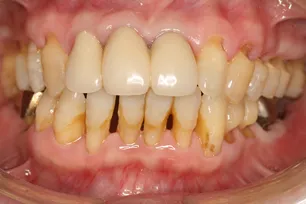

歯周病治療を行った後、画像のように「歯が長くなる」ことがあります。

これは、これまで歯茎が腫れている状態のため見えなかった部分が、歯周病治療により腫れが引き、本来の状態が見えてきた状態です。

どうしても見た目が悪くなってしまうのですが、当院では「歯肉移植術」を利用し、審美的に改善することも行っています。